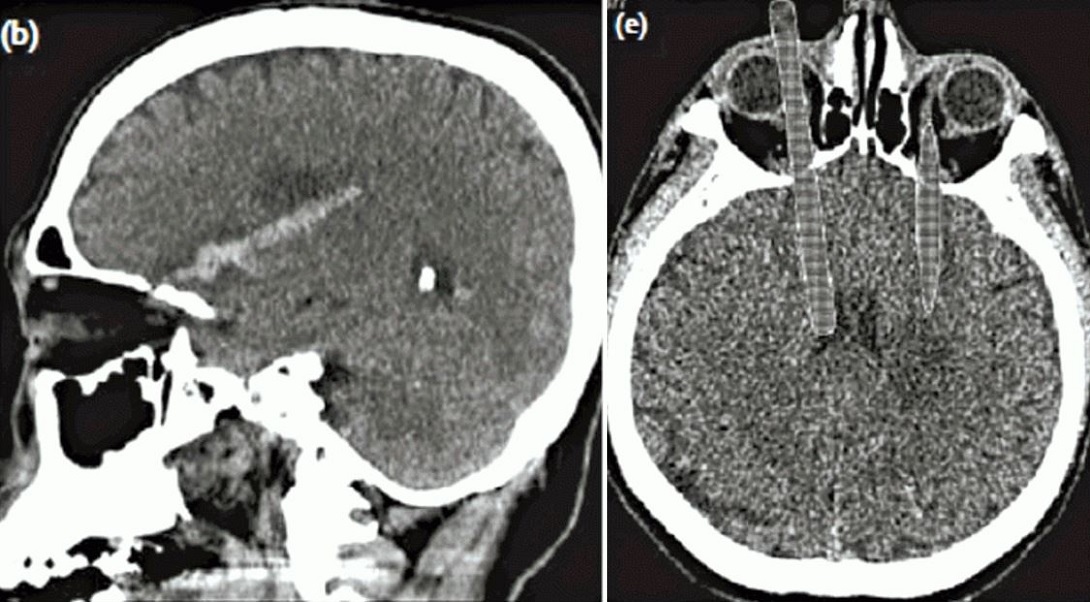

A case report in the latest Hong Kong Medical Journal states that the man — who was suffering from acute psychosis — pulled the chopsticks out himself and, incredibly, suffered no vascular or cranial nerve damage. Although the incident caused two parallel bloodstains in his brain, the patient did not require any surgery as he had also narrowly missed damaging the internal capsules at the center of his brain.

In fact, based on a recreation of the patient’s CT scan (pictured above), which was published in the journal, an opthamologist said the man likely escaped any visual impairment. According to Ming Pao, the only lasting effect that the patient experienced was slightly impaired motor function in his arms.